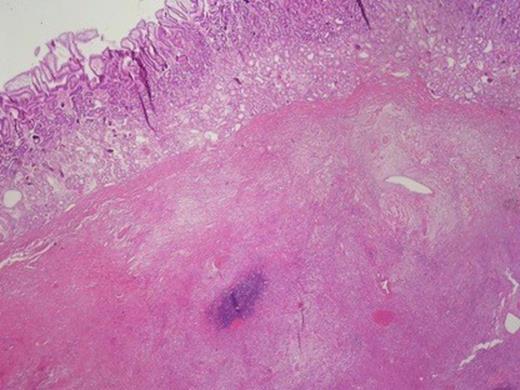

Histologically, the tumour was composed of fibroblasts that were arranged vertically. Smooth muscle cells were also recognized that apparently were remnants of the mucosal muscle layer. Also, redundant confluent lymphocytes, plasmocytes, mast cells with rare giant cell forms, as well as redundant eosinophilic granulocytes were recognized. The supernatant mucous membrane showed signs of active inflammation, and in the area of the crater, a healed ulcer was recognized. The final pathologic diagnosis was consistent with IMT that originated from the gastric wall (Figure 3).Gross examination of the nodule from the anterior wall of the fundus of the stomach showed a whitish gray elastic mass measuring 1.5x1x1cm. The tumour was identified as an incipient gastrointestinal stromal tumour that consisted of uniform neoplastic cells without nuclei atypia ((Figure 4).The node from the superior hepatic surface was identified as a syringious haemangioma. The dimensions of the haemangioma were 2x1.5x1cm and the tumour had chestnut complexion and friable texture ((Figure 5).

Gastrointestinal stromal tumour in the right and smooth muscle cells in the left.